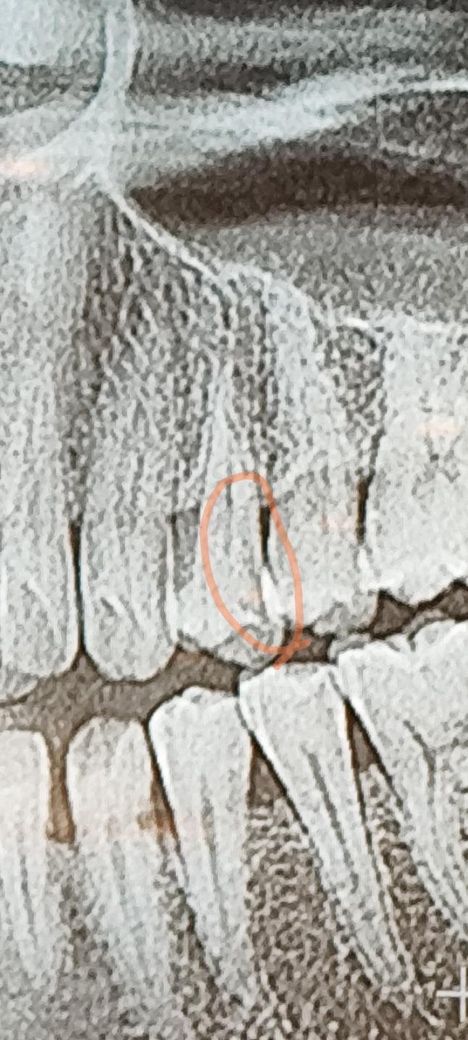

엑스레이 사진보고 충치인지 판단좀 부탁드려요

충치가 범랑질 속 안에서 생겼는데요(처음사진) 엑스레이 사진상

동그라미친 옆면부분의 검은 음영부분은 뿌리쪽까지

번진 충치인가요?치아를 많이 파야하는건지 궁금합니다

사진으로 봤을 경우에는 인접면에 충치가 생긴것으로 보입니다.

뿌리까지 진행되지는 않은것으로 보이며 충치를 제거하는 도중에 신경이 노출이 된다면 신경치료후 크라운 치료가 필요할 수 있습니다.

그레보이진 않습니다 다만 더 정확히 보려면 파노라마 말고 치근단 엑스레이 사진을 찍어봐야 합니다